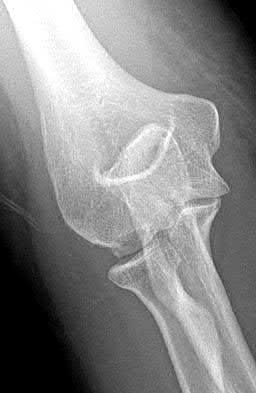

1012) A 54-year-old woman sustains the injury seen in Figures 71a and 71b. The injury involves her nondominant extremity. What should the patient be told regarding her expected outcome?

Corrent answer: 3

This is a Bado type 2 (posterior) Monteggia lesion, which is associated with higher rates of complications than other types of Monteggia lesions. The injury is associated with indirect high-energy trauma and less often pathologic causes. Of the four types of Monteggia lesions, the type 2 or posterior type is associated with the worst prognosis. These injuries are best treated surgically with dorsal plating of the ulna and reduction with fixation or arthroplasty of the radial head. The major complications seen with this injury pattern are nonunion and plate failure. Almost all patients have some loss of elbow range of motion. Satisfactory results based on functional scores for this injury are not universal. Neurologic injury and ulnohumeral instability are unusual with this type of injury. Full functional recovery is not expected with nonsurgical management.